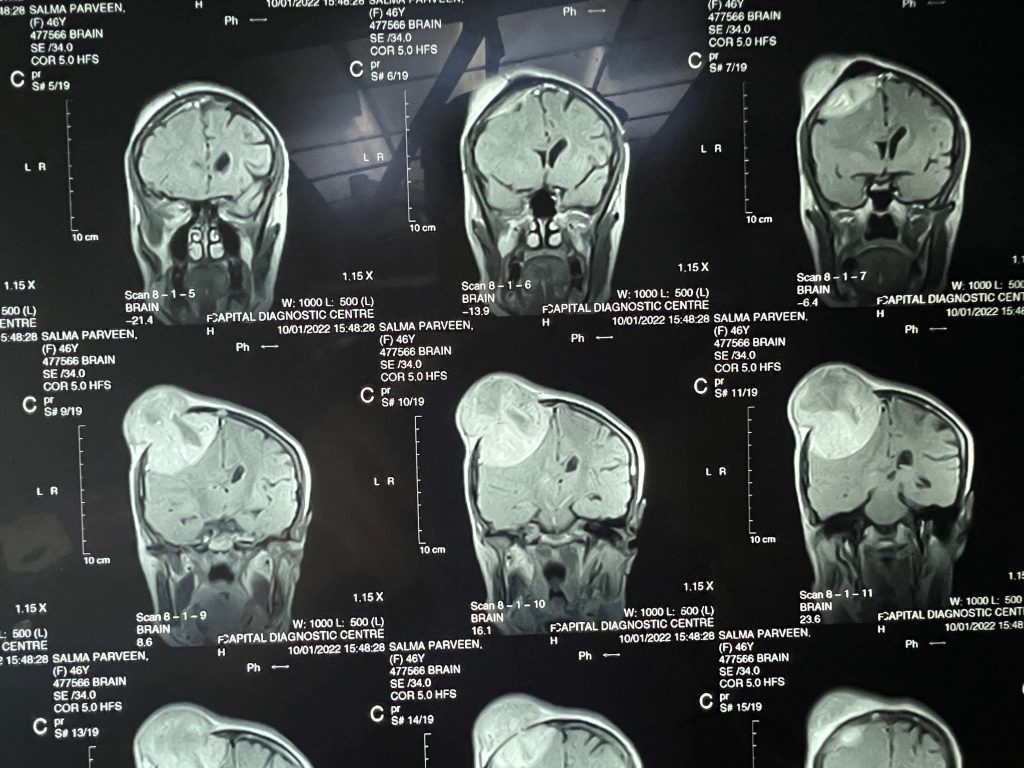

Brain Tumors Overview

- Meningiomas

- Gliomas

- Pituitary Tumors

- Posterior fossa tumors

- Orbital Tumors(Eye)

- Ventricular tumor

- Brain Cysts